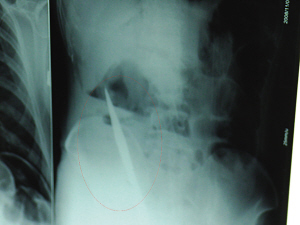

X光片上,尖刀清晰可见。

从男子体内取出的尖刀足足有19厘米长。

6日上午,记者在徐州矿务集团总医院重症监护室见到了这名男子,目前他虽然已经恢复了意识,但还不能开口说话,需要呼吸机辅助呼吸。据医生介绍,4日中午12时左右,这名男子因服毒轻生被紧急送到医院进行抢救,之前,这名男子已经在当地乡镇医院进行了近20小时的治疗,但效果不佳。“病人被转院到矿总院时已神志不清,血压极低,处于休克状态。”救护人员给男子洗胃、初步处理以后,发现男子呼吸急促,于是赶紧给他拍片检查。结果让所有的医生大吃一惊,竟有一把尖状异物横在该男子腹腔内!当天下午5时30分,轻生男子被推上了手术台。经过40多分钟的手术,该男子腹腔被打开,手术医生发现,男子体内的金属状异物竟然是一把长19厘米的尖刀!

医生告诉记者,手术后,医生在病人身上并未发现刀痕,最后,经过检查发现,在该男子直肠处找到穿孔。医生从医学角度分析后认为,这把尖刀应该是从肛门插入直肠的。医生说,因为病人抢救及时,尖刀并未伤及要害,所以暂时保住了性命,但后期可能会出现腹腔感染、AIDS、器官衰竭等多种并发症。